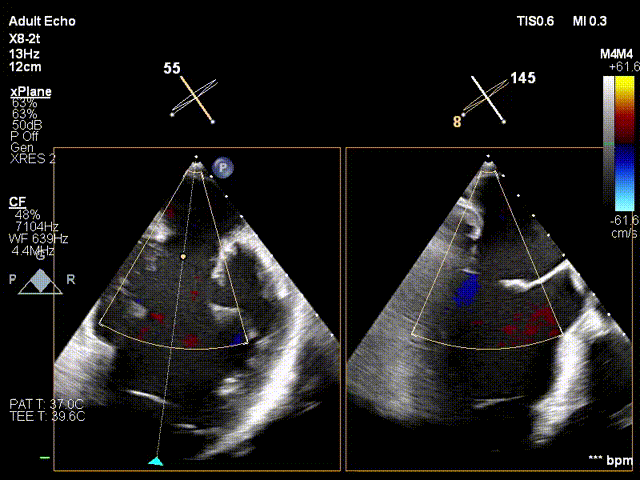

L侧有残余反流

于L侧2偏3区置入第一枚短宽夹

瓣叶捕获

两枚夹子中间有残余反流1+

解离后3D评估组织桥稳定

反流未增加

TMPG:1mmHg

肺静脉逆流消失